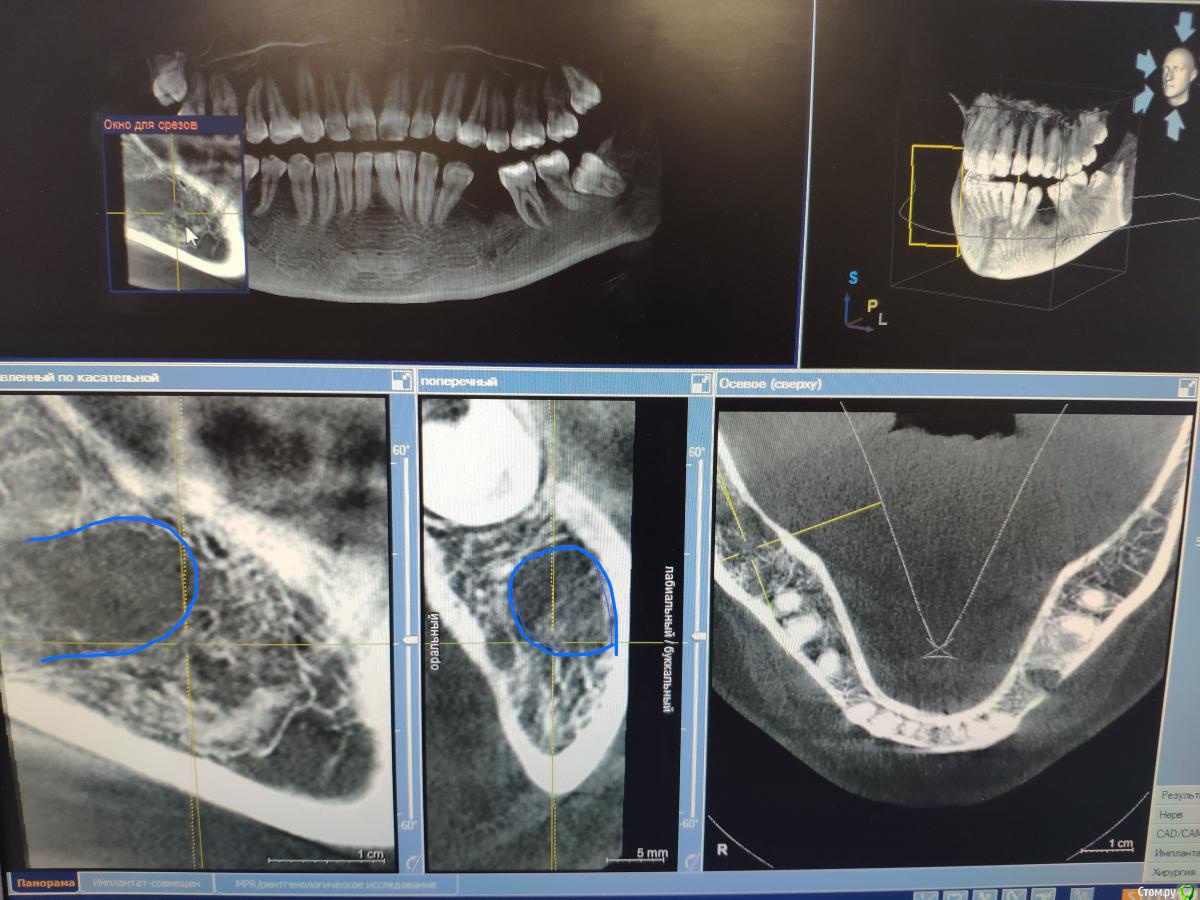

Женька Опубликовано 9 июня, 2020 Поделиться Опубликовано 9 июня, 2020 Тоже спрошу, чтобы не плодить темы.Пришла вот такая пациентка, удаление 28 февраля 2020. Думаю, что ничего страшного и можно ставить не взирая на образование, по крайней мере, мне видится, что это не апексы... тень думаю, потому, что лунка всё еще в стадии заживленияЧто скажете, коллеги? Ссылка на комментарий

Irouil Опубликовано 9 июня, 2020 Поделиться Опубликовано 9 июня, 2020 Как минимум один кусочек чего-то белого на последнем срезе есть Можно ещё прицелку посмотреть. А что с анамнезом? Ссылка на комментарий

Женька Опубликовано 9 июня, 2020 Поделиться Опубликовано 9 июня, 2020 Как минимум один кусочек чего-то белого на последнем срезе есть Можно ещё прицелку посмотреть. А что с анамнезом?В анамнезе у бабушки Cr желудка.Прицела к сожалению нету пломбировочный материал? мне кажется он В остальном считает себя здоровой, по врачам не бегает, на учётах не состоит. Во время удаления (удалял не я) делали прицелы после, и тоже увидели это образование (со слов пациентки). Ссылка на комментарий

Fin Опубликовано 9 июня, 2020 Автор Поделиться Опубликовано 9 июня, 2020 В анамнезе у бабушки Cr желудка.Прицела к сожалению нету пломбировочный материал? мне кажется он В остальном считает себя здоровой, по врачам не бегает, на учётах не состоит. Во время удаления (удалял не я) делали прицелы после, и тоже увидели это образование (со слов пациентки).Удаление 28 было, а когда сделано КТ?. По мне да, лунка в стадии заживления, если вы про дистальное образование то это одонтома, а вот на верхушке гребня что то есть. Думаю что ничего страшного,сделаете прицельный снимок перед имплантацией и если что во время операции уберете. Ссылка на комментарий

red_butler Опубликовано 9 июня, 2020 Поделиться Опубликовано 9 июня, 2020 Что скажете, коллеги? я бы удалил и возможно на гистологию отправил 2 Ссылка на комментарий

Женька Опубликовано 9 июня, 2020 Поделиться Опубликовано 9 июня, 2020 Удаление 28 было, а когда сделано КТ?. По мне да, лунка в стадии заживления, если вы про дистальное образование то это одонтома, а вот на верхушке гребня что то есть. Думаю что ничего страшного,сделаете прицельный снимок перед имплантацией и если что во время операции уберете.Кт от 8 июня. я бы удалил и возможно на гистологию отправилИз-за анамнеза родословной? Ссылка на комментарий

red_butler Опубликовано 9 июня, 2020 Поделиться Опубликовано 9 июня, 2020 Кт от 8 июня. Из-за анамнеза родословной?Нет, новообразование имеет оболочку, не хотелось бы удалять имея там имплант 1 Ссылка на комментарий

Женька Опубликовано 9 июня, 2020 Поделиться Опубликовано 9 июня, 2020 Записал срезы Кт, вижу что-то похожее на корень с ярким материалом в области края гребня. И образование, по плотности как кортика. + лунки заживающие. Ссылка на комментарий

red_butler Опубликовано 9 июня, 2020 Поделиться Опубликовано 9 июня, 2020 https://youtu.be/1pW5wBBAbls Записал срезы Кт, вижу что-то похожее на корень с ярким материалом в области края гребня. И образование, по плотности как кортика. + лунки заживающие.Похоже на корень. А есть снимки до удаления? И настораживает, зачем коллеги делали rg после удаления.., Ссылка на комментарий

Женька Опубликовано 9 июня, 2020 Поделиться Опубликовано 9 июня, 2020 Похоже на корень. На верхушке гребня с ярким рентгеноконтрастным материалом? или где-то в другом месте? А есть снимки до удаления? Была вроде ОПТГ, попробую вытянуть у пациентки.И настораживает, зачем коллеги делали rg после удаления..,Именно из-за этого плотного образования. Ссылка на комментарий

Irouil Опубликовано 10 июня, 2020 Поделиться Опубликовано 10 июня, 2020 я бы удалил и возможно на гистологию отправилТут мне кажется верное решение Похоже на какую-то цементому не удалённую, но все же Ссылка на комментарий

Женька Опубликовано 10 июня, 2020 Поделиться Опубликовано 10 июня, 2020 Тут мне кажется верное решение Похоже на какую-то цементому не удалённую, но все жеВозможно меня неправильно поняли) у бабушки пациентки был Cr в анамнезе...Или разницы нет и не стоит имплантировать пока не уберу образование?Но тогда другой вопрос, как оптимальнее его вытащить? или не важно и всё равно придется аугментировать и ждать? Ссылка на комментарий

Irouil Опубликовано 10 июня, 2020 Поделиться Опубликовано 10 июня, 2020 Возможно меня неправильно поняли) у бабушки пациентки был Cr в анамнезе...Или разницы нет и не стоит имплантировать пока не уберу образование?Но тогда другой вопрос, как оптимальнее его вытащить? или не важно и всё равно придется аугментировать и ждать?Про бабушку я понял. Но если эта штука осумкована (а на орто до тоже так кажется), то вокруг импланта пойдёт расти ее капсула, а не кость. По крайней мере есть такой риск. Ну а на гистологию всегда лучше сдать, чем не сдать Ссылка на комментарий